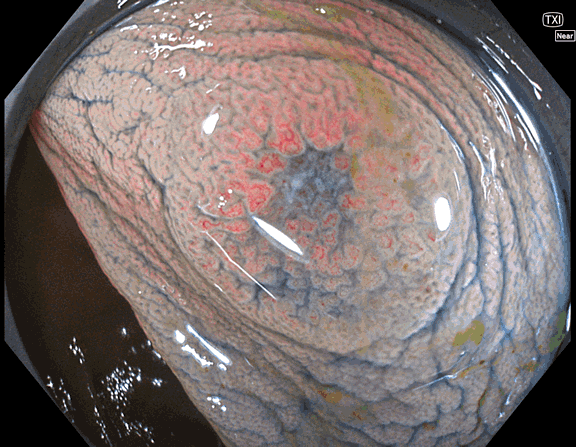

(1)最高画質機(1500型)の使用

「平坦陥凹型ポリープ(Ⅱb、Ⅱc)の発見率」を定期的に公開

30分以上の観察時間を保証( 一般的な医療機関の観察時間は5分前後)。

検査後に「観察時間(抜去時間)」を記録した写真をお渡しします。

●使用スコープの機種(EZ1500DI)と観察時の鎮静剤使用について

現在、最も高性能な1500型スコープを使用。このスコープは大学病院には必ず常備されていますが、ほとんど使われません。太いため使いこなすには技術が必要だからです。